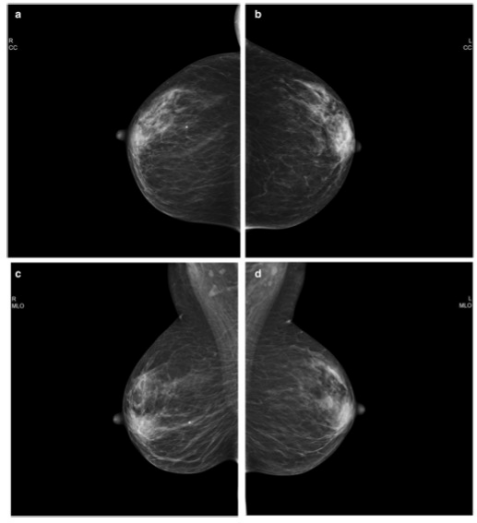

圖 使用PGMI系統(tǒng)歸類為 "完美 "的乳腺鉬靶照片。 a 以病人協(xié)助的壓縮模式獲得的右CC視圖。b 以標準壓縮模式獲得的左CC視圖。c 以病人協(xié)助的壓縮模式獲得的右MLO視圖

本項前瞻性隨機對照試驗在2017年9月-2019年12月期間進行。參與者是50至69歲的無癥狀女性,每位參與者均參加了第二輪或后續(xù)的乳腺鉬靶檢查。通過隨機分配,一個乳腺接受SC檢查,另一個乳腺接受PAC檢查。根據(jù)顱底(CC)視圖的10個標準和縱側(cè)斜(MLO)視圖的8個標準,圖像質(zhì)量被評估為完美、良好、中等或不足(PGMI)。進行皮爾遜卡方檢驗,如有必要則進行Yates校正,以比較不同壓縮模式的圖像質(zhì)量。

共有444名參與者被納入其中(平均[±標準差]年齡,60[±4.9]歲)。在CC視圖中,PAC和SC模式的PGMI百分比沒有差異(完美,37% [162/444] vs 37% [163/444];良好,1% [5/444] vs 2% [9/444];中等,62% [277/444] vs 61% [271/444];不足,0% vs 0. 2% [1/444]; p = .88)或MLO視圖(完美,53% [237/444] vs 56% [247/444]; 良好,22% [99/444] vs 22% [97/444]; 中等,23% [102/444] vs 22% [98/444]; 不夠,1% [6/444] vs 0.5% [2/444]; p = .72)。當(dāng)按橫向分層或按PGMI標準分析時,也沒有發(fā)現(xiàn)統(tǒng)計學(xué)差異。